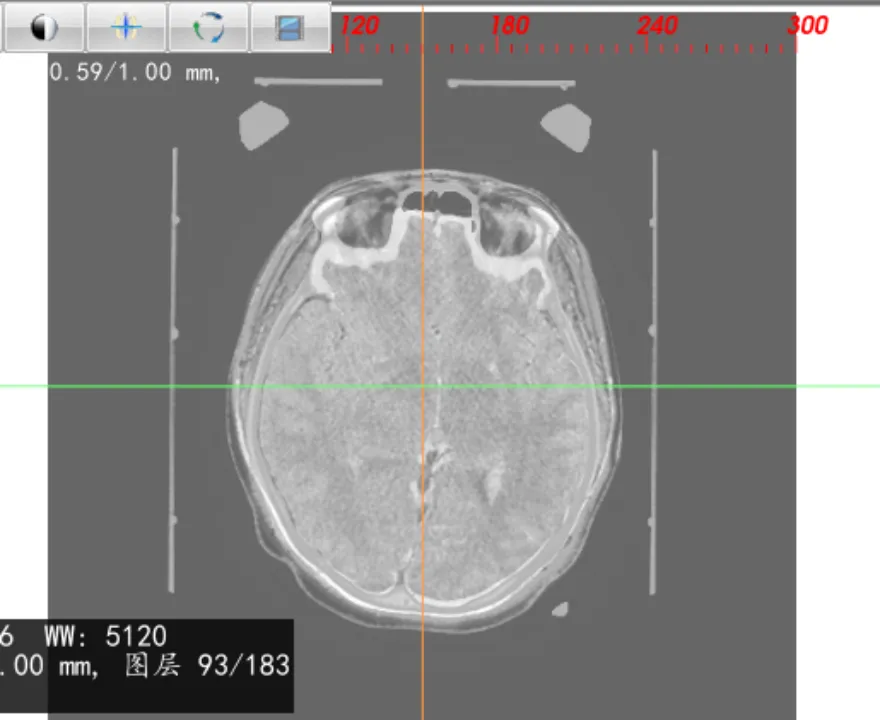

图像融合

导入多个序列,可对图像进行一键融合,生成融合序列,如:进行CT、磁共振融合,设定融合比例,可对CT或磁共振显示的权重进行调整。

0% 50% 100%